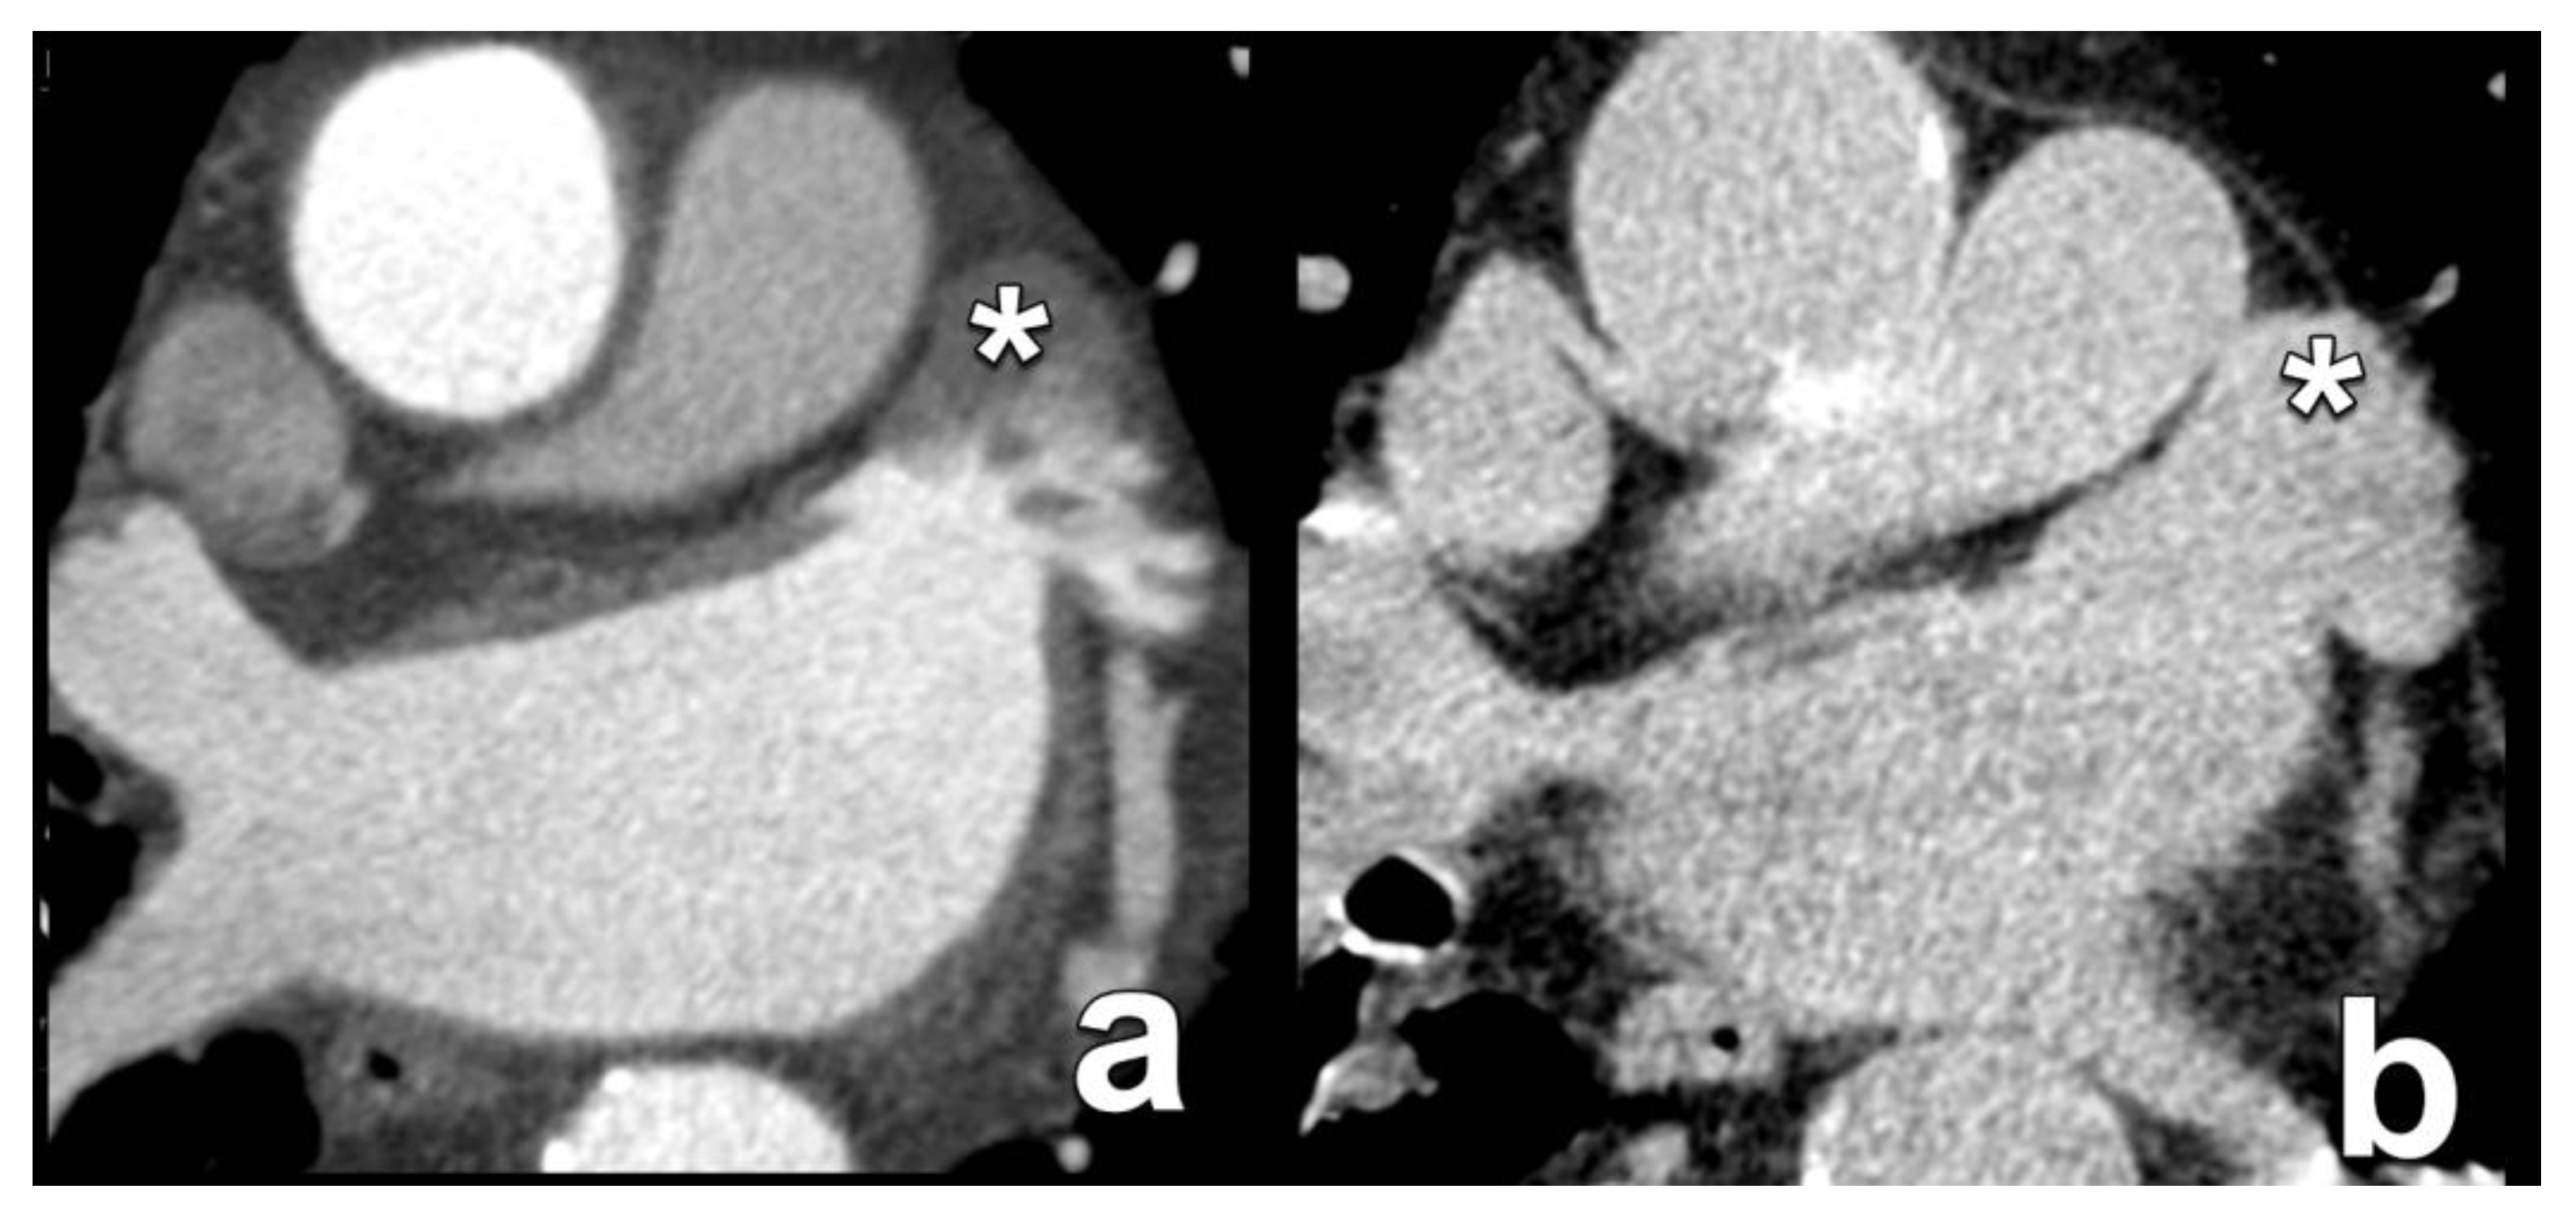

| Sinus of Valsalva dimensions | Long- and short-axis cross-sectional diameters Largest cross-sectional diameter Commissure-to-cusp diameter Height of the coronary sinus | The aortic sinus needs to be wide enough to accommodate displaced native leaflet calcifications during the deployment of the THV. |

| Coronary ostia heights | Distance from annular plane to bottom of left and right coronary ostia | As a rule of thumb, a minimum diameter of 10 mm is considered the threshold to avid ostial coronary obstruction by migrated leaflet calcifications. |